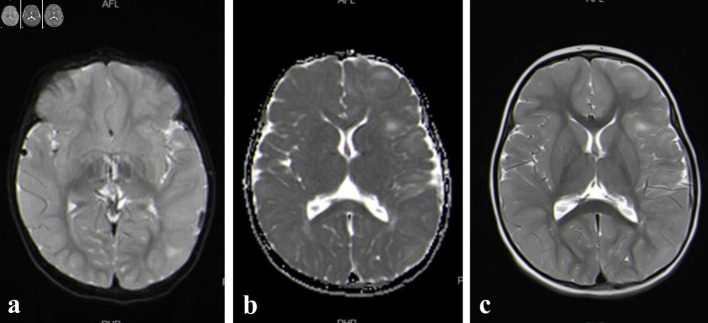

结节性硬化症(TSC)是一种常染色体显性遗传的神经皮肤疾病。由于错构瘤在不同器官中形成,其特点是多系统受累。TSC2基因突变是该疾病最常见的原因,与TSC1基因突变相比,与更严重的神经系统症状相关。然而,在我们的病例中,我们报告了一名2- 5个月大的女孩在TSC2基因外显子37侧剪接位点检测到的罕见突变。她在1个月大时出现全身异常的肢体运动。对遗传数据库的回顾显示,在文献中没有关于该基因的先前报告。她的诊断经TCS基因面板证实。后来,她发展为肾细胞癌。这些病例由一个多学科团队管理,包括一名儿科医生、一名儿科神经科医生、一名儿科心脏病专家、一名儿科血液肿瘤学专家和一名儿科外科专家。TSC患儿的总体预后是可变的,取决于症状的严重程度,尤其是神经系统表现。

Tuberous sclerosis complex (TSC) is a neurocutaneous disorder inherited in autosomal dominant manner. It is characterized by multisystem involvement due to the formation of hamartomas in different organs. TSC2 gene mutations are the most common cause of the disease and are associated with more severe neurological symptoms compared to TSC1 gene mutations. However, in our case, we are reporting a rare mutation detected at the flanking splice site of exon 37 in the TSC2 gene in a 2-year-5-month-old girl. She presented to the emergency department at the age of 1 month with generalized abnormal body movements. A review of genetic databases revealed no prior reports of this gene in the literature. Her diagnosis was confirmed by gene panel for TCS. Later, she developed renal cell carcinoma. Such cases are managed by a multidisciplinary team including a pediatrician, a pediatric neurologist, a pediatric cardiologist, a pediatric hematology-oncology specialist, and specialist in pediatric surgery. The overall prognosis of children with TSC is variable and dependent on the severity of symptoms, especially neurologic manifestations.